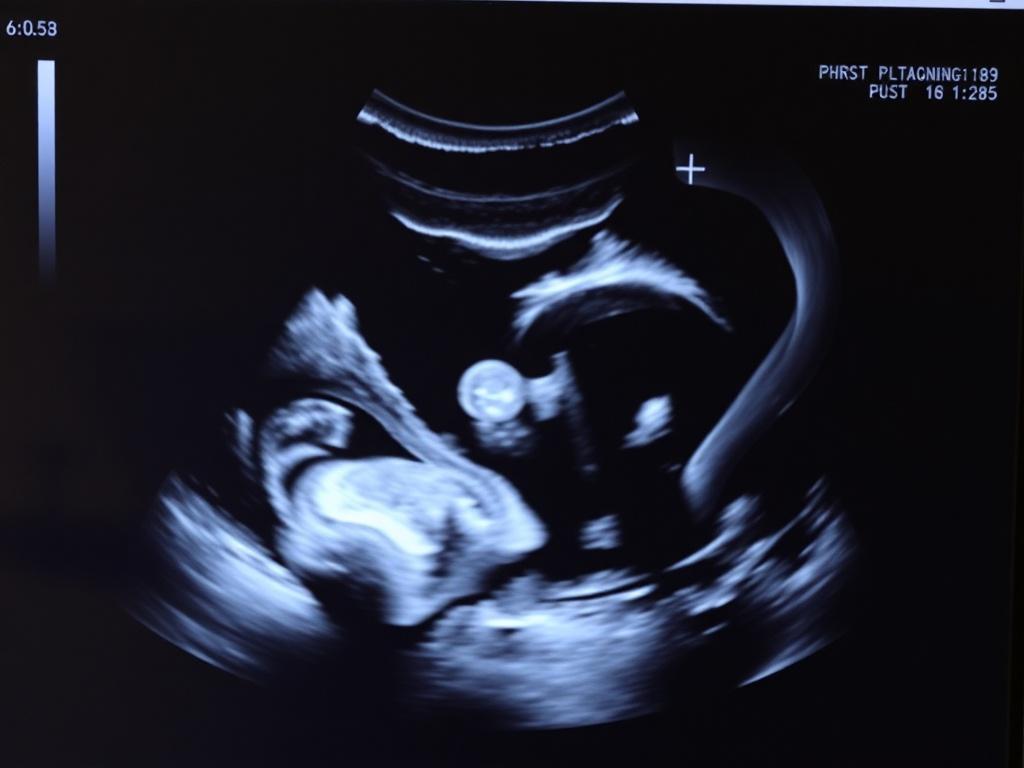

УЗИ покажет состояние органов, которые отвечают за вынашивание ребенка. Врач посмотрит матку, яичники, маточные трубы. Проверит, нет ли каких-то проблем. Например, воспалений, кист или миом. Эти проблемы могут мешать забеременеть или выносить малыша. Лучше узнать о них заранее.

Что увидит врач

Врач оценит размер и форму матки. Посмотрит, нет ли особенностей, которые могут осложнить беременность. Проверит яичники. Убедится, что в них созревают яйцеклетки. Посмотрит, нет ли кист, которые иногда мешают зачатию. Оценит толщину эндометрия. Это внутренний слой матки. К нему должна прикрепиться оплодотворенная яйцеклетка.